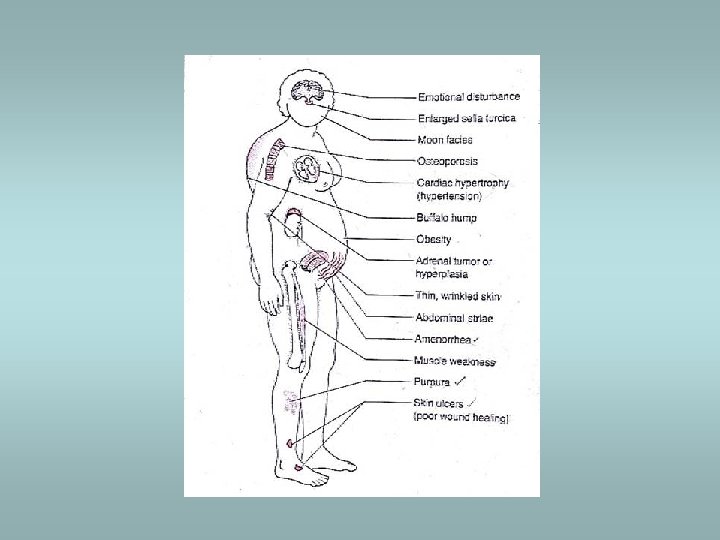

Cushing’s syndrome Causes: ü Administration of exogenous glucocorticoids – most common ü Pituitary hypersecretion of ACTH (Cushing’s disease) – adenoma ü Ectopic ACTH secretion – small cell carcinoma !! Histology: ü Crooke’s hyaline changes within pituitary basophils Clinically: ü Central obesity, moon facies, fatigability, hirsutism, hypertension, osteoporosis, cutaneous striae